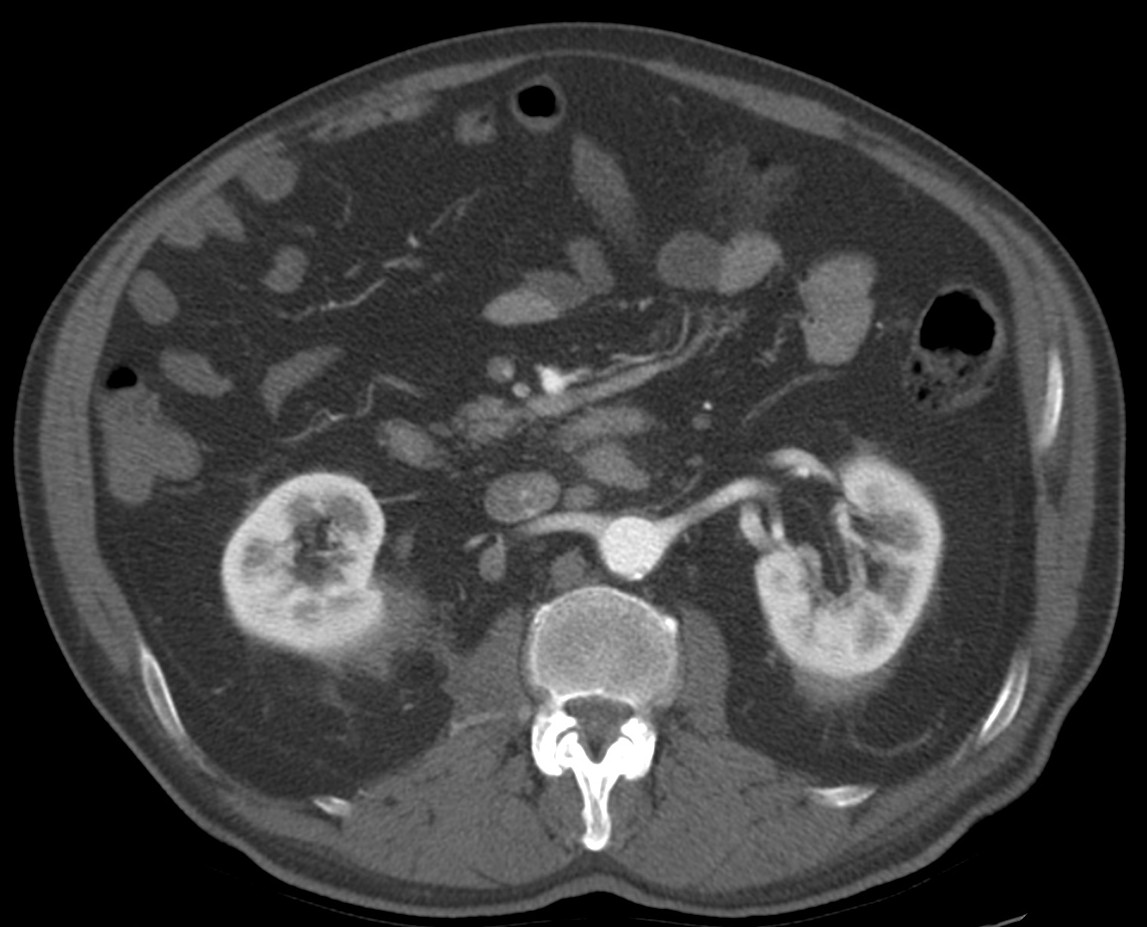

CASO 2: Paciente de 68 años con dolor en flanco izquierdo, fiebre y malestar general. A la exploración existe enrojecimiento de la piel con sensación de masa palpable y puño percusión muy positiva.

El paciente es alégrico al Iodo. Se realiza TC sin contraste para ampliar estudio.

Todos estos hallazgos están en relación con una Pielonefritis Xantunogranulomatosa que afecta al riñón derecho junto con una colección que ha fistulizado a región lumbar.